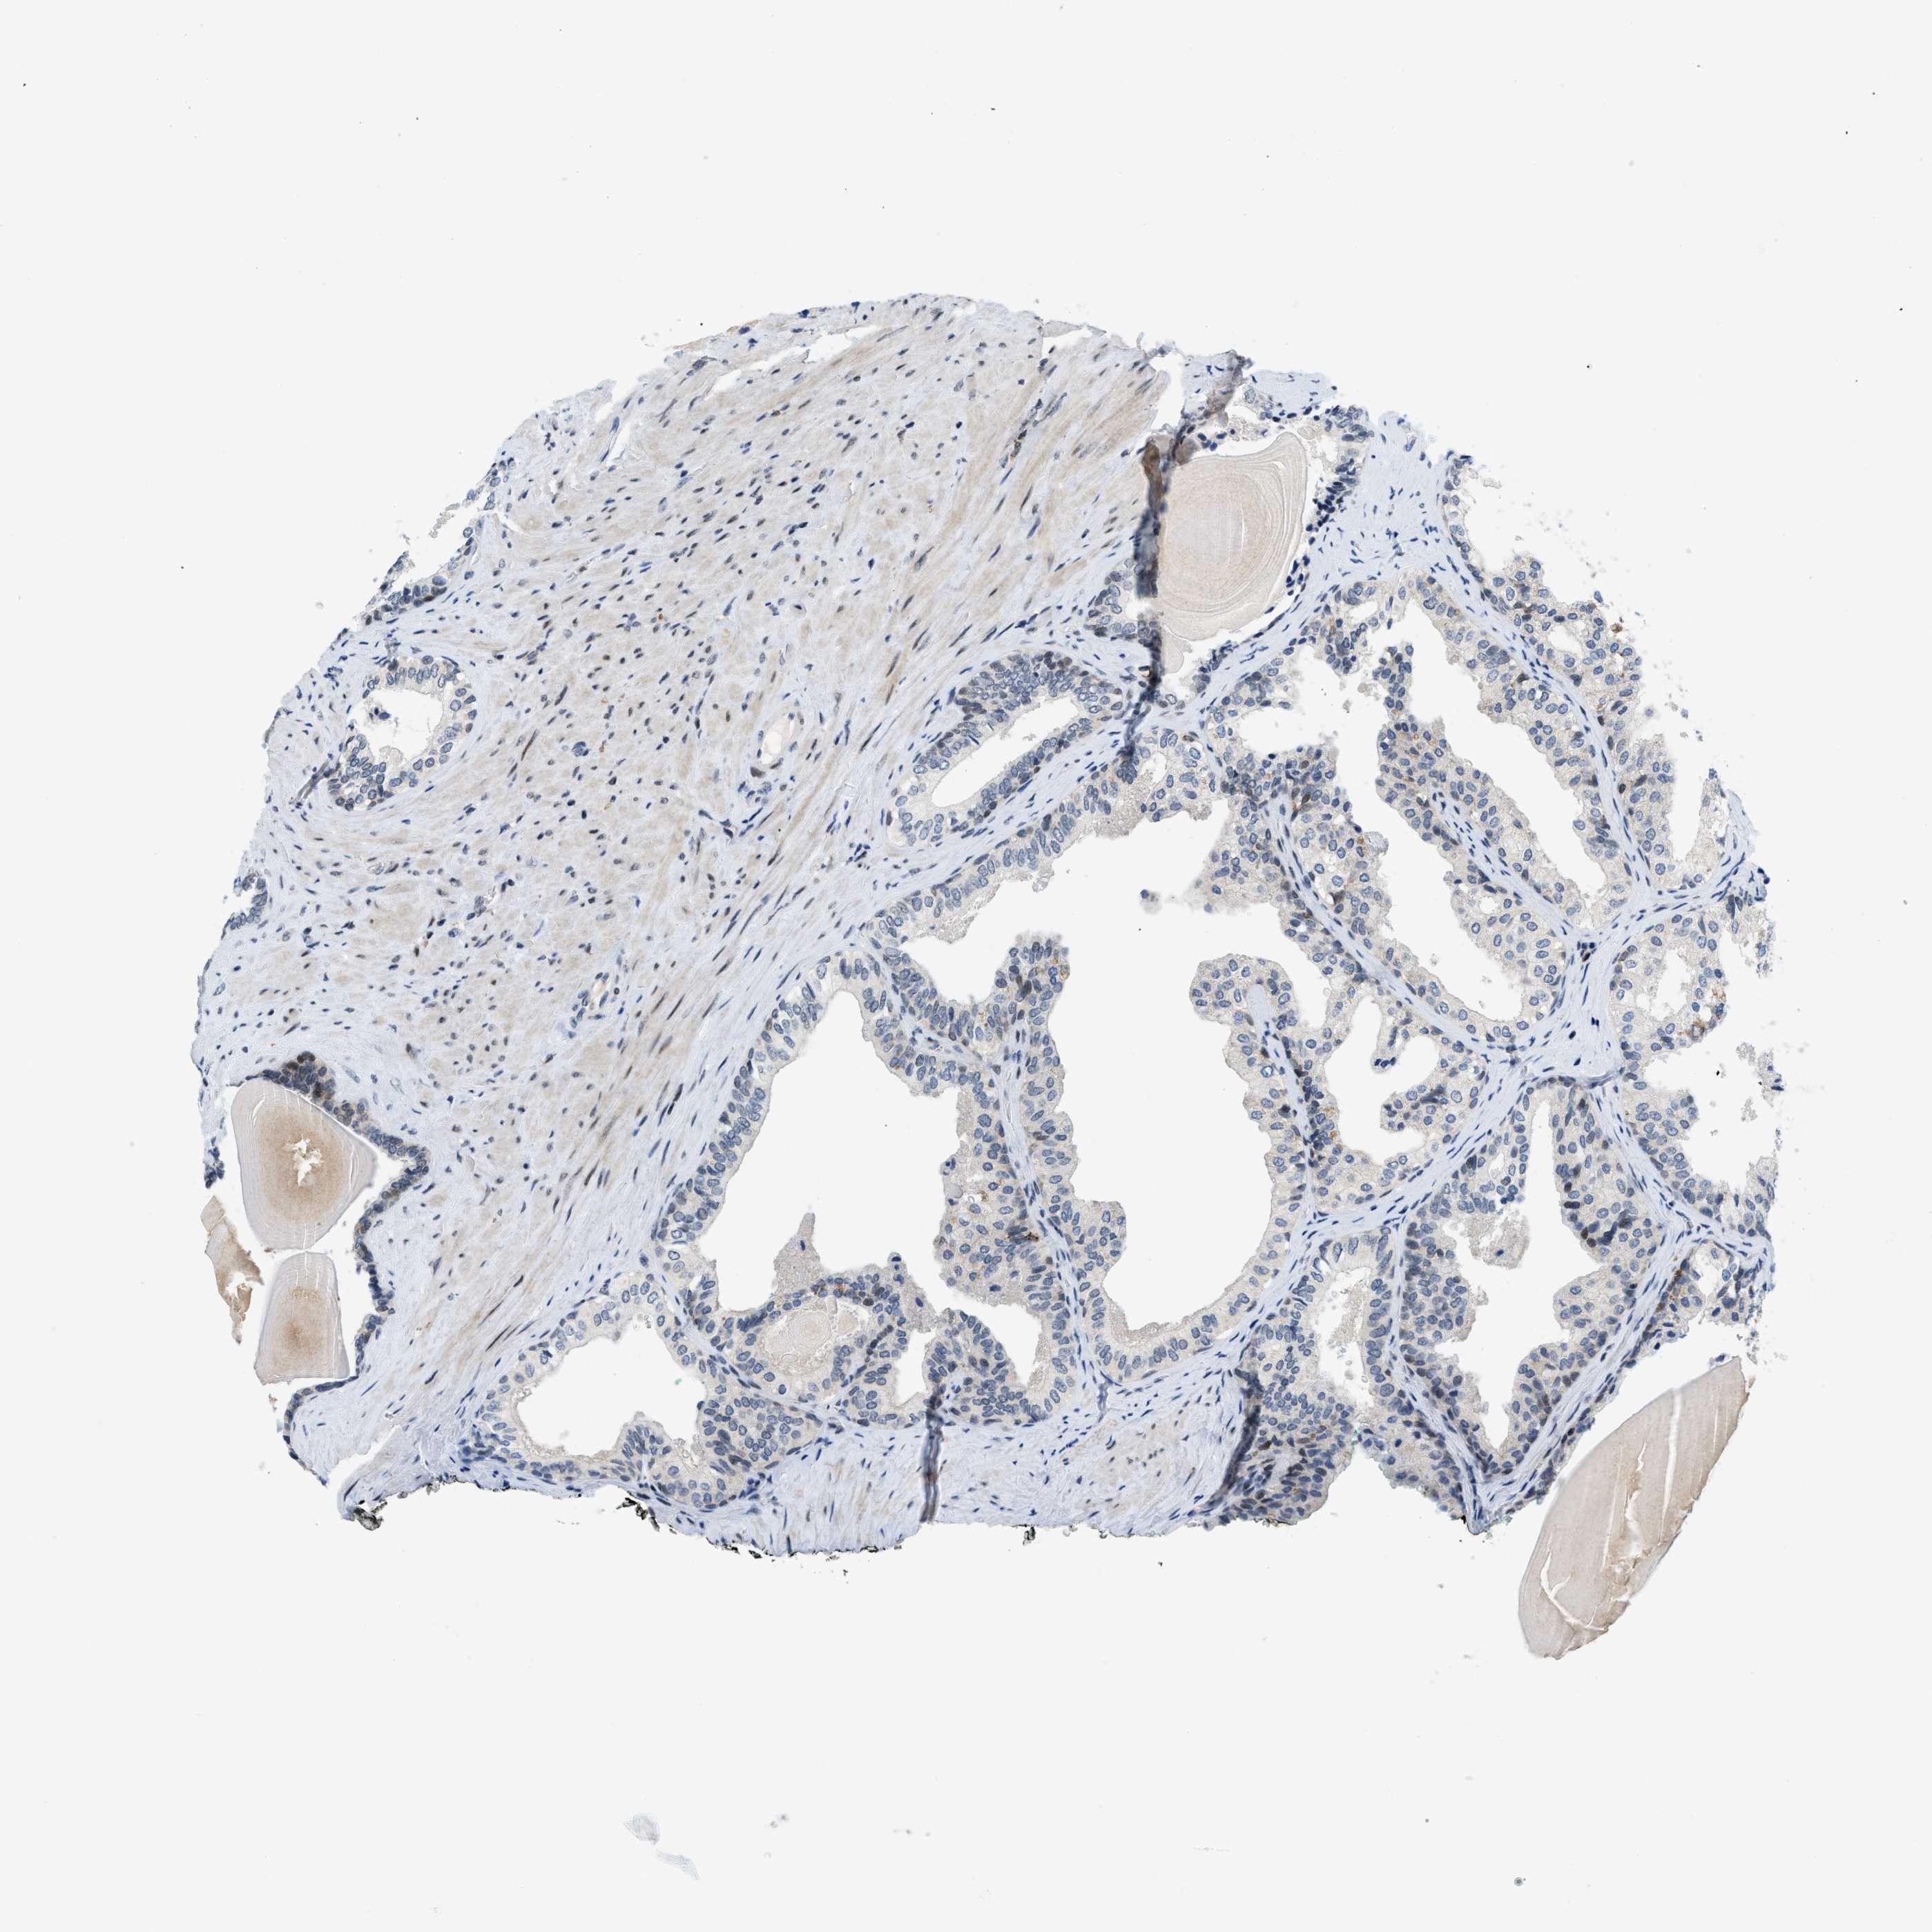

PROSTATE CANCER - Protein expressioni

A mouse-over function shows sample information and annotation data. Click on an image to view it in a full screen mode. Samples can be filtered based on level of antibody staining by selecting one or several of the following categories: high, medium, low and not detected. The assay and annotation is described here.

Antibody stainingi

Antibody staining in the annotated cell types in the current human tissue is reported as not detected, low, medium, or high, based on conventional immunohistochemistry profiling in selected tissues. This score is based on the combination of the staining intensity and fraction of stained cells.

Each image is clickable and will lead to virtual microscopy that enables deeper exploration of all samples and also displays staining intensity scores, fraction scores and subcellular localization as well as patient and tissue information for each sample.

Antibody CAB016136

Antibody CAB017773

Staining

High

Medium

Low

Not detected

Intensity

Strong

Moderate

Weak

Negative

Quantity

>75%

75%-25%

<25%

None

Location

Nuclear

Cytoplasmic/membranous

Cytoplasmic/membranous,nuclear

Adenocarcinoma, Low grade

Adenocarcinoma, High grade